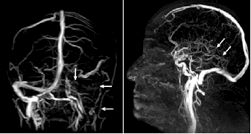

图2.左图示左静脉窦及颈静脉均无血流;

右图示深部静脉系统无血流(→)。

图3. 脑静脉系统解剖示意图。蓝色血管代表深静脉系统。